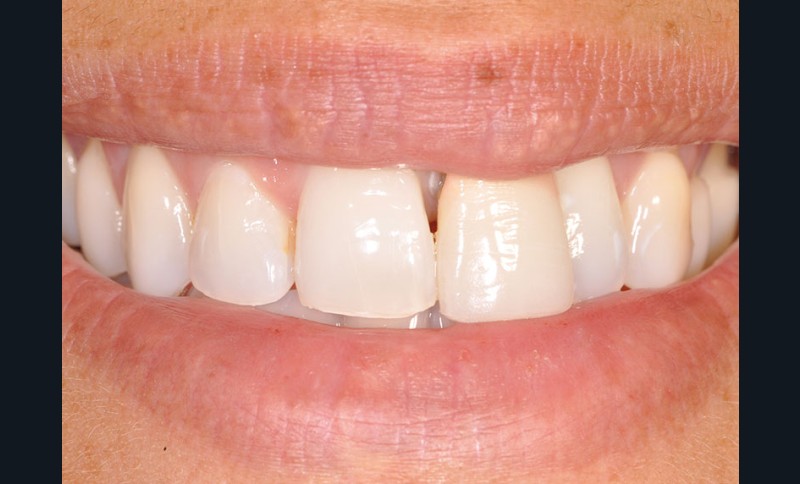

Une patiente âgée de 32 ans, en bonne santé générale et non fumeuse, est adressée pour réhabilitation esthétique et fonctionnelle du secteur antérieur, conséquence d’un trauma facial remontant à seize ans, au cours duquel la dent 21 a été expulsée et réimplantée. Dans un souci esthétique, deux couronnes céramo-métalliques ont été fabriquées successivement au cours du déplacement progressif de la dent.

L’examen clinique montre que l’incisive centrale maxillaire gauche (21) est en exfoliation vestibulaire, elle présente une mobilité 2 de sa portion coronaire et interfère dans sa fonction (fig. 1, 2).